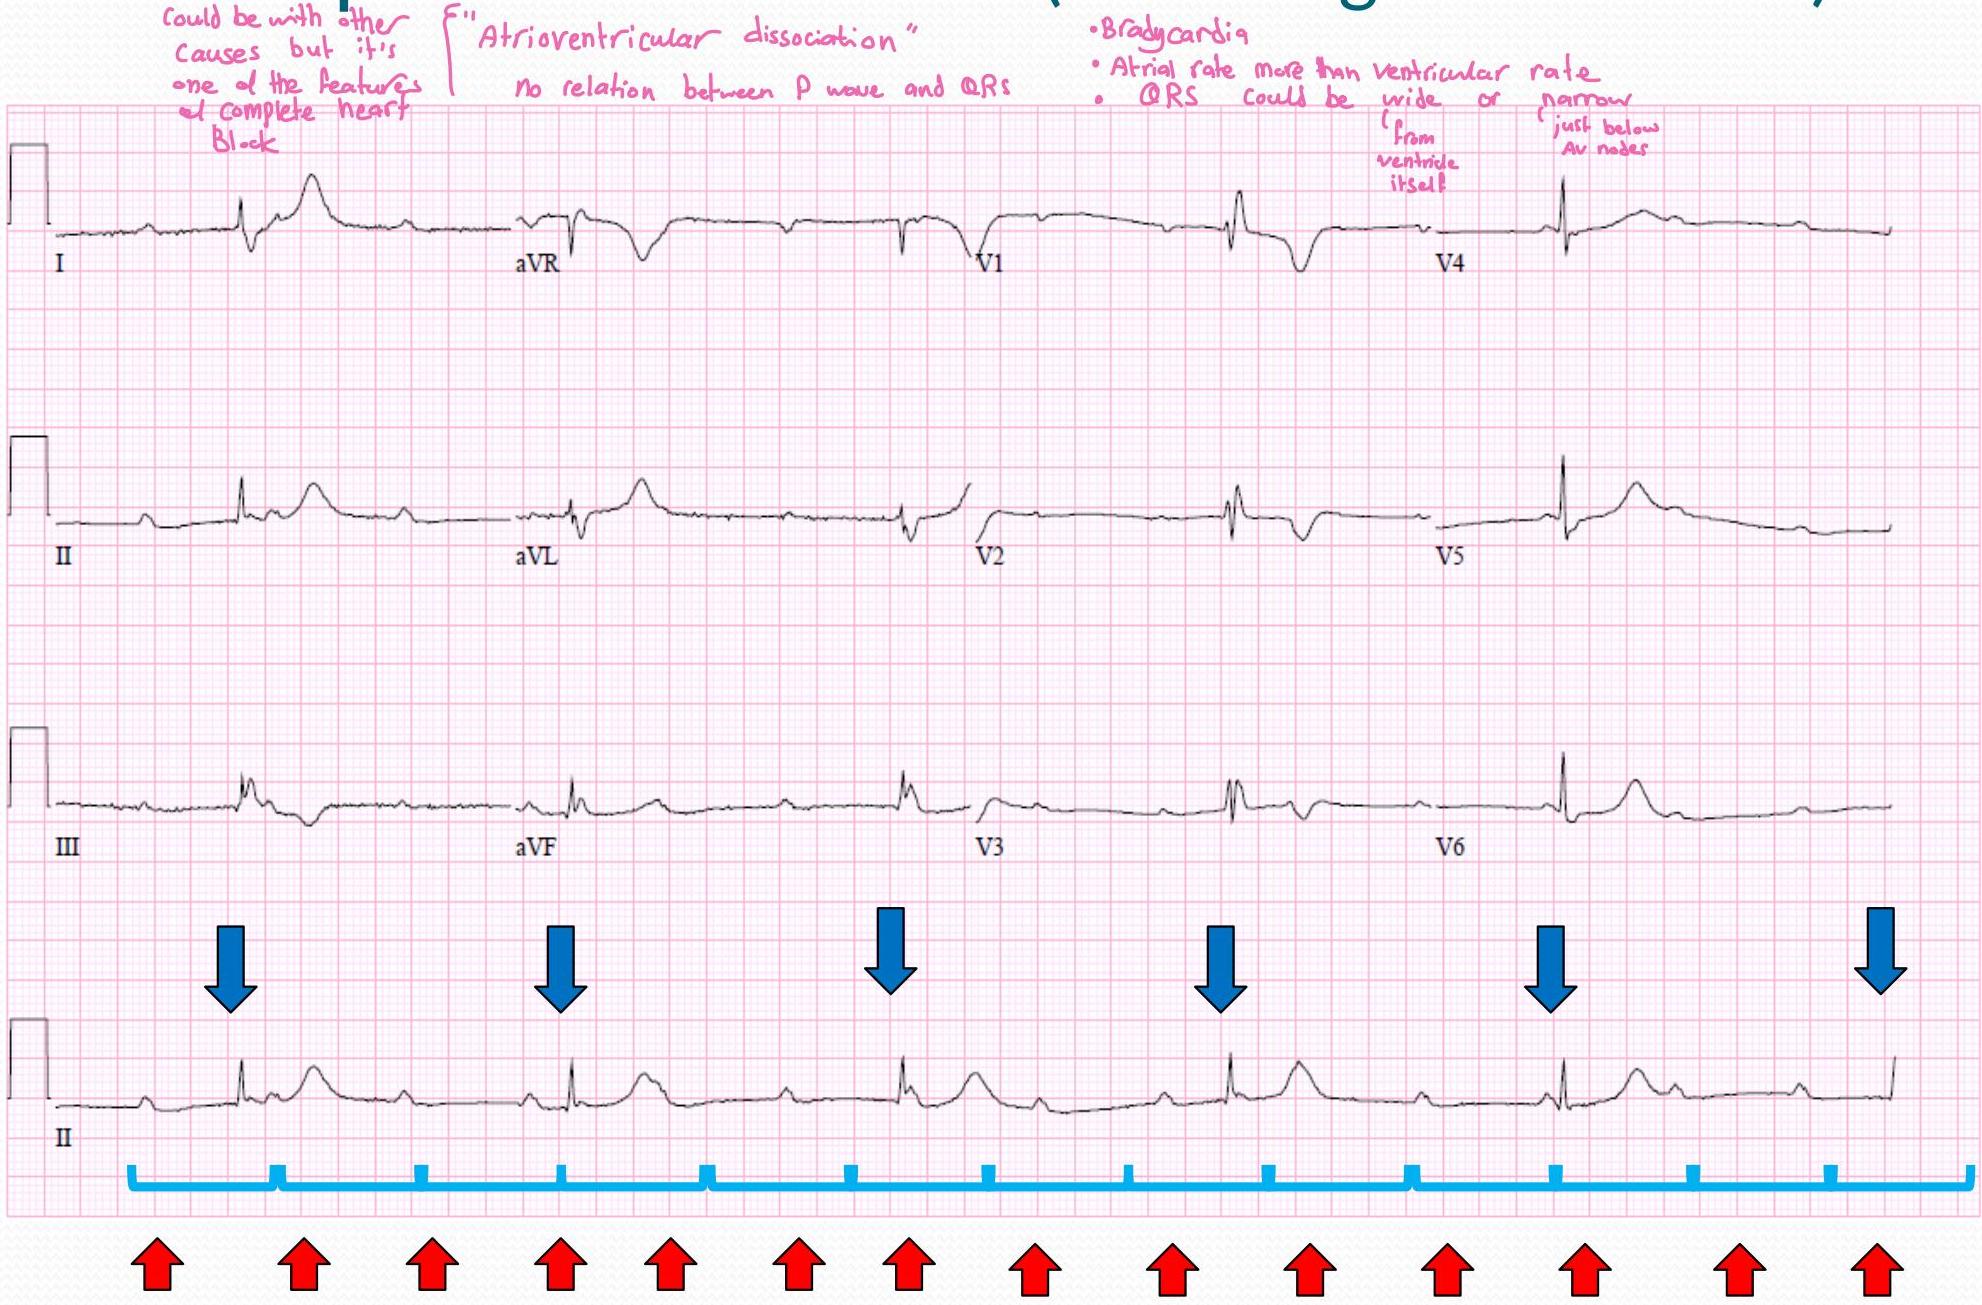

Third Degree AV Block (Complete Heart Block)

- could be with other causes but it’s one of the features of complete heart block

- “Atrioventricular dissociation” no relation between P wave and QRS

- Bradycardia

- Atrial rate more than ventricular rate

- QRS could be wide or narrow (from ventricle itself, just below AV nodes)

Causes:

- SLE in the mother antibodies will skip the placenta

- Rheumatic Carbitis

- IHD

- Digitalis

Treatment:

- ett: Race maker

| P Wave | PR Interval (in seconds) | QRS (in seconds) | Characteristics |

|---|---|---|---|

| Normal but not related to QRS | None | N/A | No relationship between P&RS |